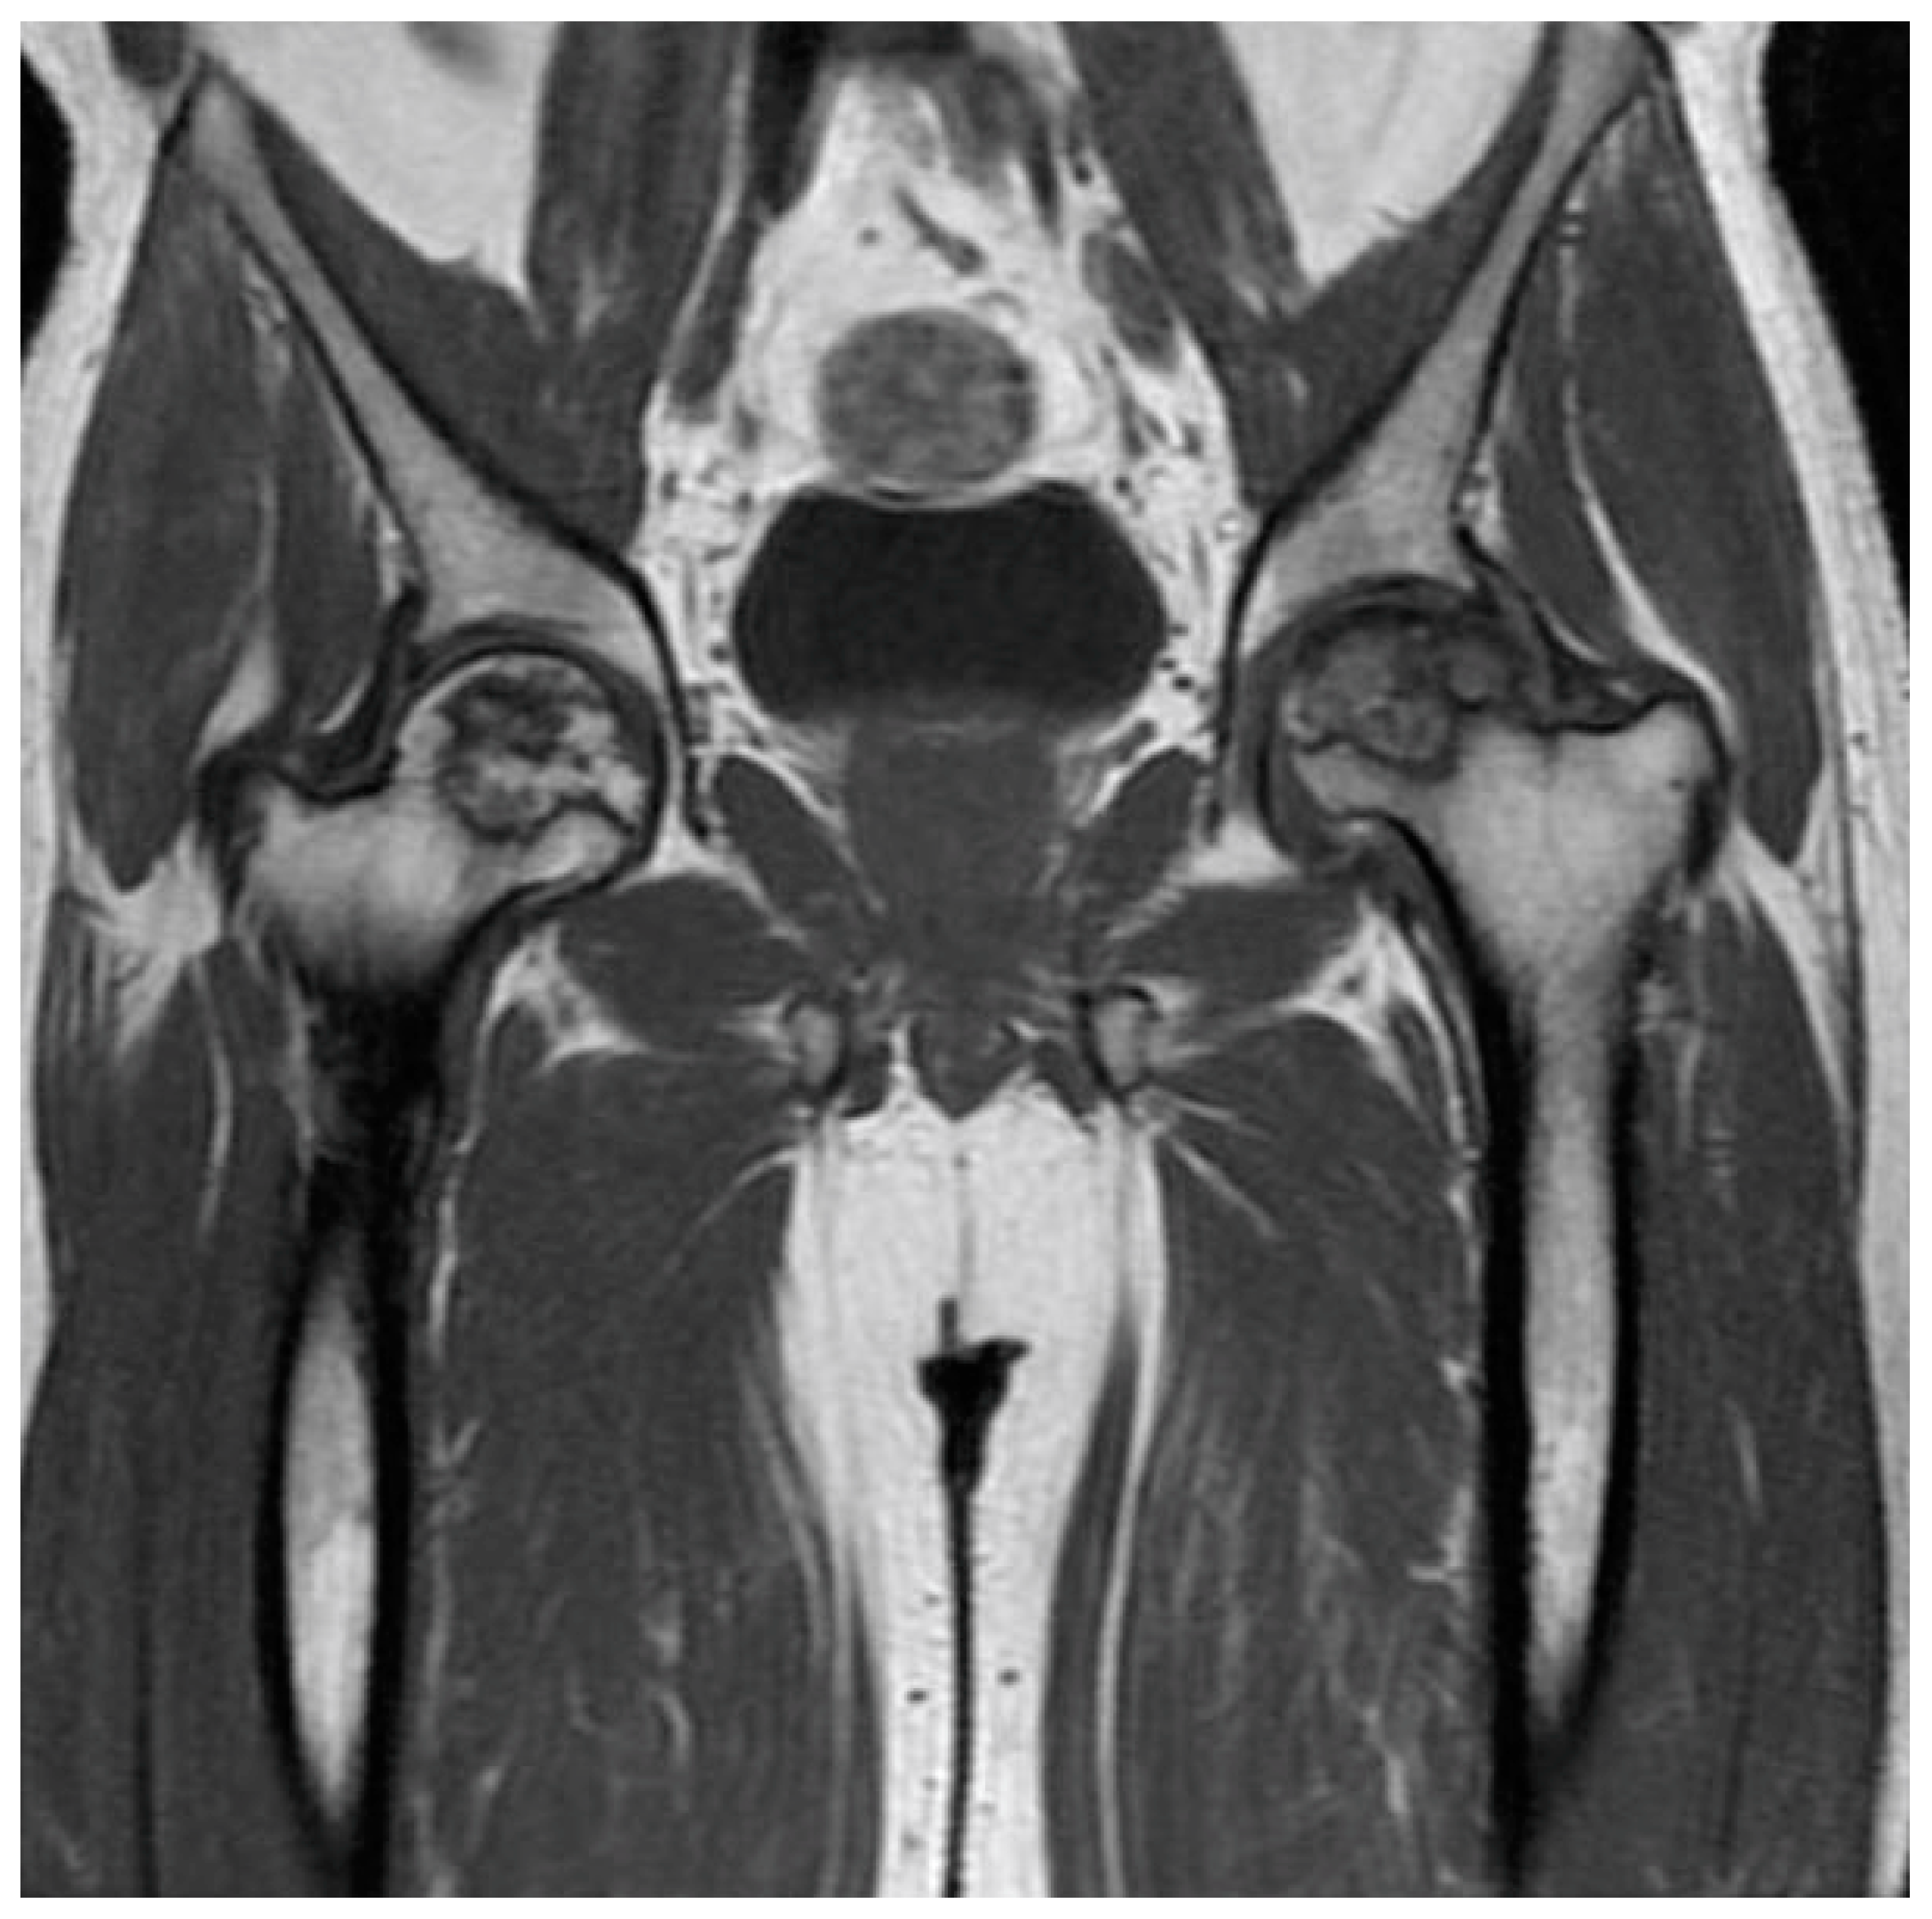

| MRI features | T1-weighted images display a single-density, low-signal intensity line. T2-weighted images display a high-intensity line with early necrotic-viable bone interface. | In T1-weighted images, the progeny is typically hypointense. In T2-weighted images, the progeny is mostly heterogeneous; this sequence can assess the integrity of articular cartilage, reactive marrow edema in the parent bone, and fluid or cystic changes at the parent-progeny interface. |